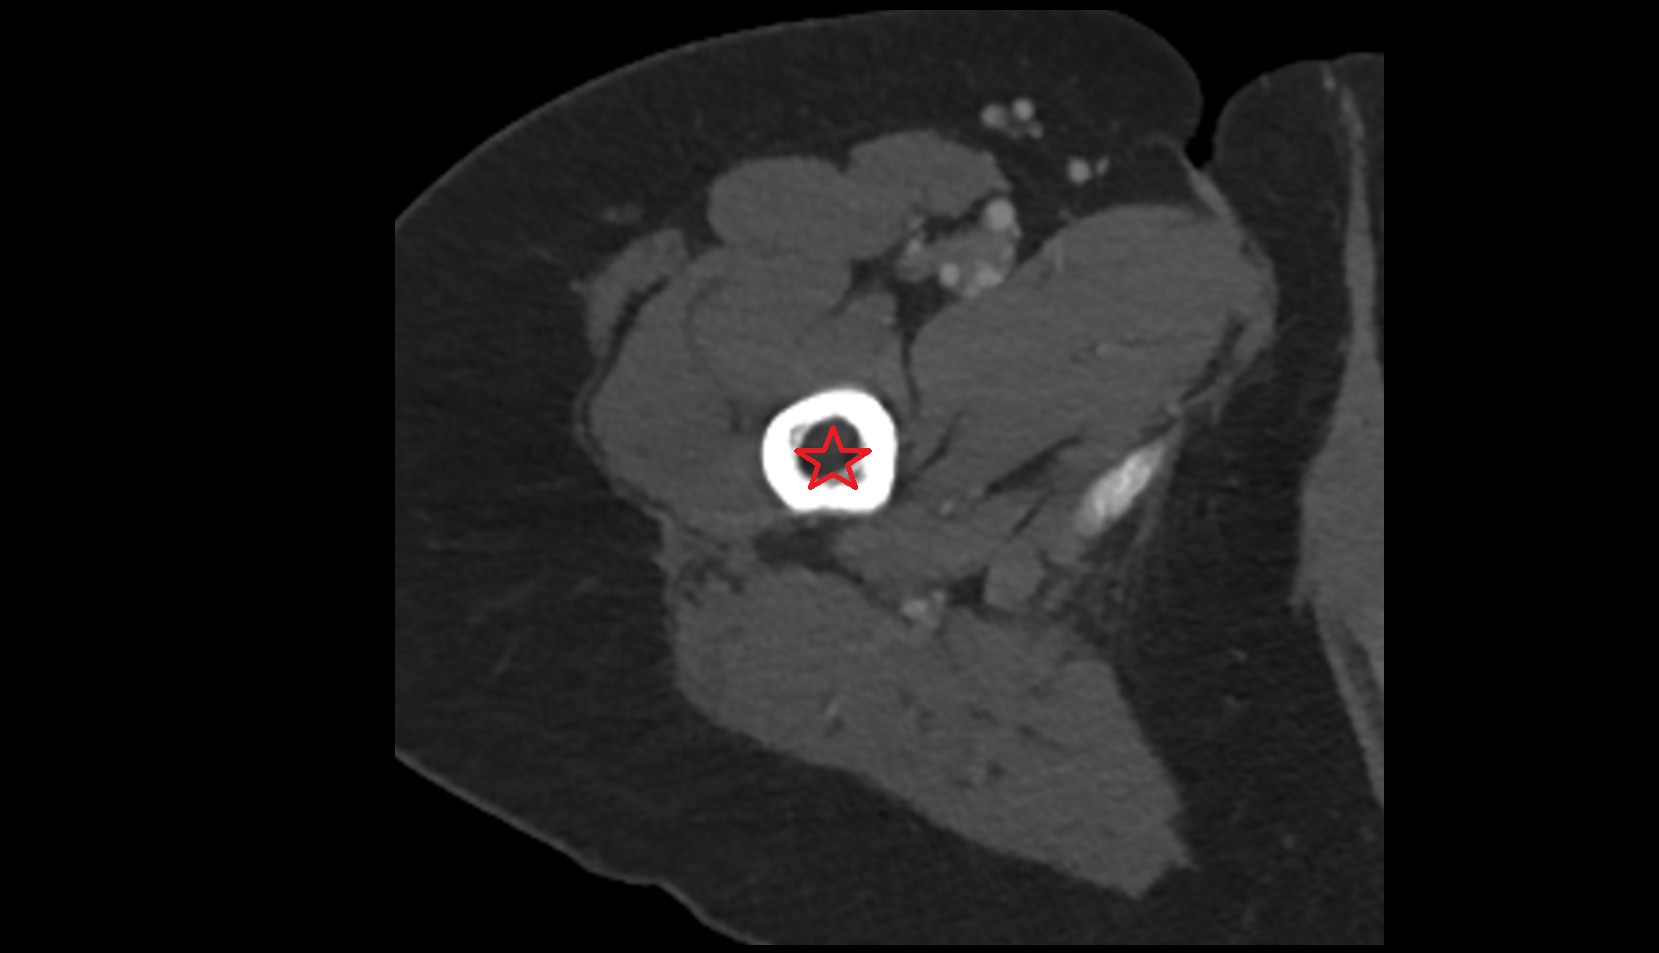

- Peripheral zone of prostate

- Anterior Fibromuscular Stroma of prostate

- Central zone of prostate

- Transitional zone of prostate